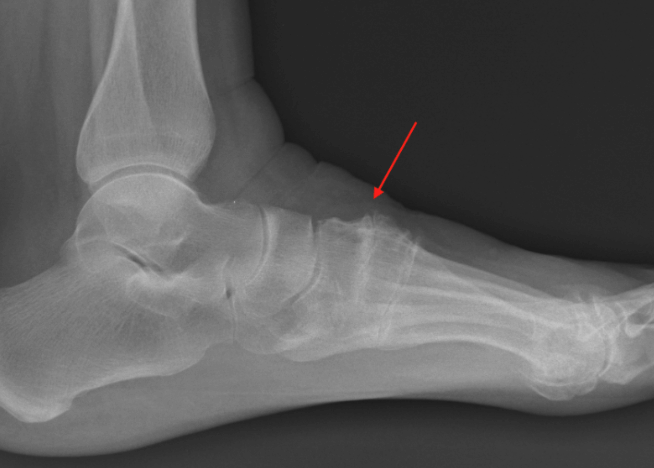

Imaging is essential for diagnosis. Weight-bearing X-rays typically demonstrate joint space narrowing, bone spurs, sclerosis, or collapse of the arch. CT scans may be used to better define the extent of arthritis and assist with surgical planning, while MRI can evaluate associated soft-tissue pathology in select cases.